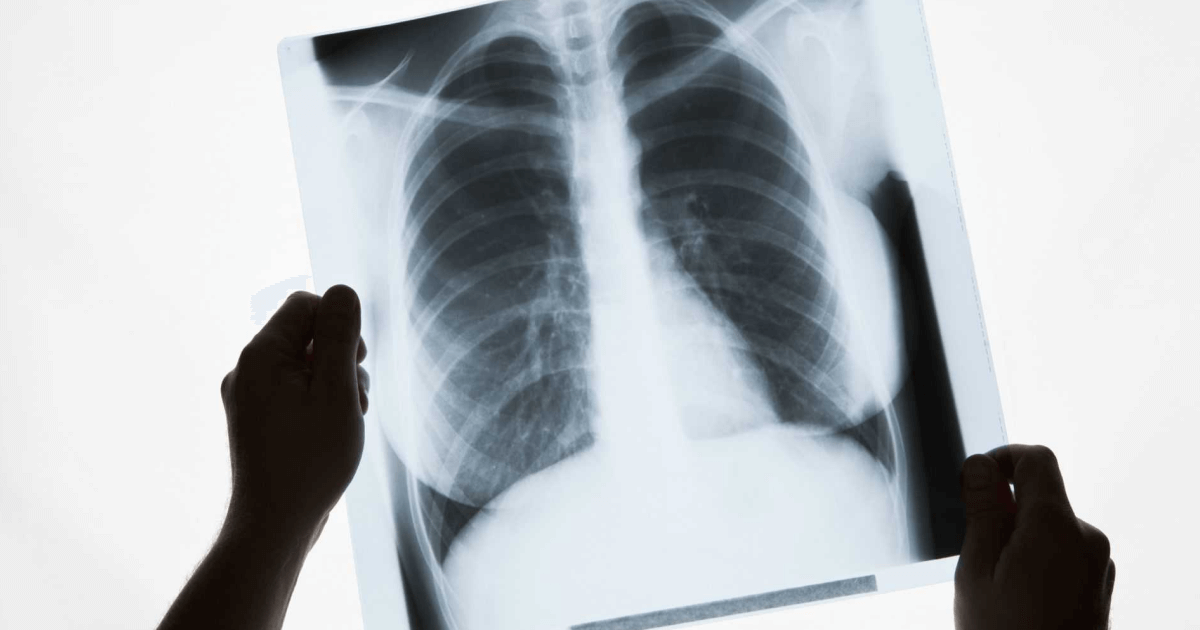

Ученые из Национального института онкологии США, при поддержке коллег из Канады и Европы, провели исследование, выяснив, почему пациенты, которые не курят, болеют раком легких.

В ходе исследование специалисты секвенировали геномы клеток опухолей 232 некурящих людей с немелкоклеточным раком легких. Порядка 189 из них страдали от самой распространенной формы рака легких — аденокарциномы, тогда как 36 столкнулись с карциноидной опухолью.

Так, в результате научной работы было установлено, что онкология легких у некурящих людей связана с наборами мутаций, спровоцированных естественными процессами в организме. Помимо прочего исследователи вывели три новых подтипа рака легких у некурящих больных — “пиано», “меццо-форте» и “форте». Отмечается, что из всех случаев рака легких на некурящих приходится от 10 до 25%.